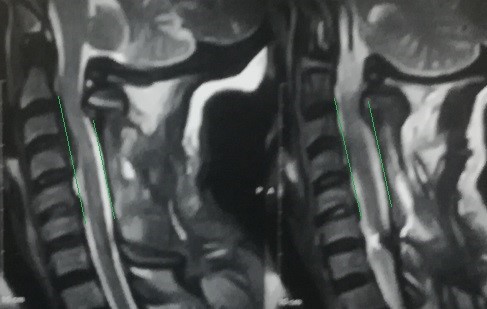

A case of a female patient in the fifth decade of life suffering from quadrilateral weakness and increased neurological reflexes due to her ossification or calcification of the dura mater against the third and fourth cervical vertebrae, and multiple cervical herniated discs as shown on CT and MRI scans.

A successful surgery was performed to expand the cervical nerve canal and stabilize the cervical vertebrae from the back, which resulted in decompression of the spinal cord in the cervical vertebrae, as shown by CT scans and MRI after surgery, and the patient recovered.